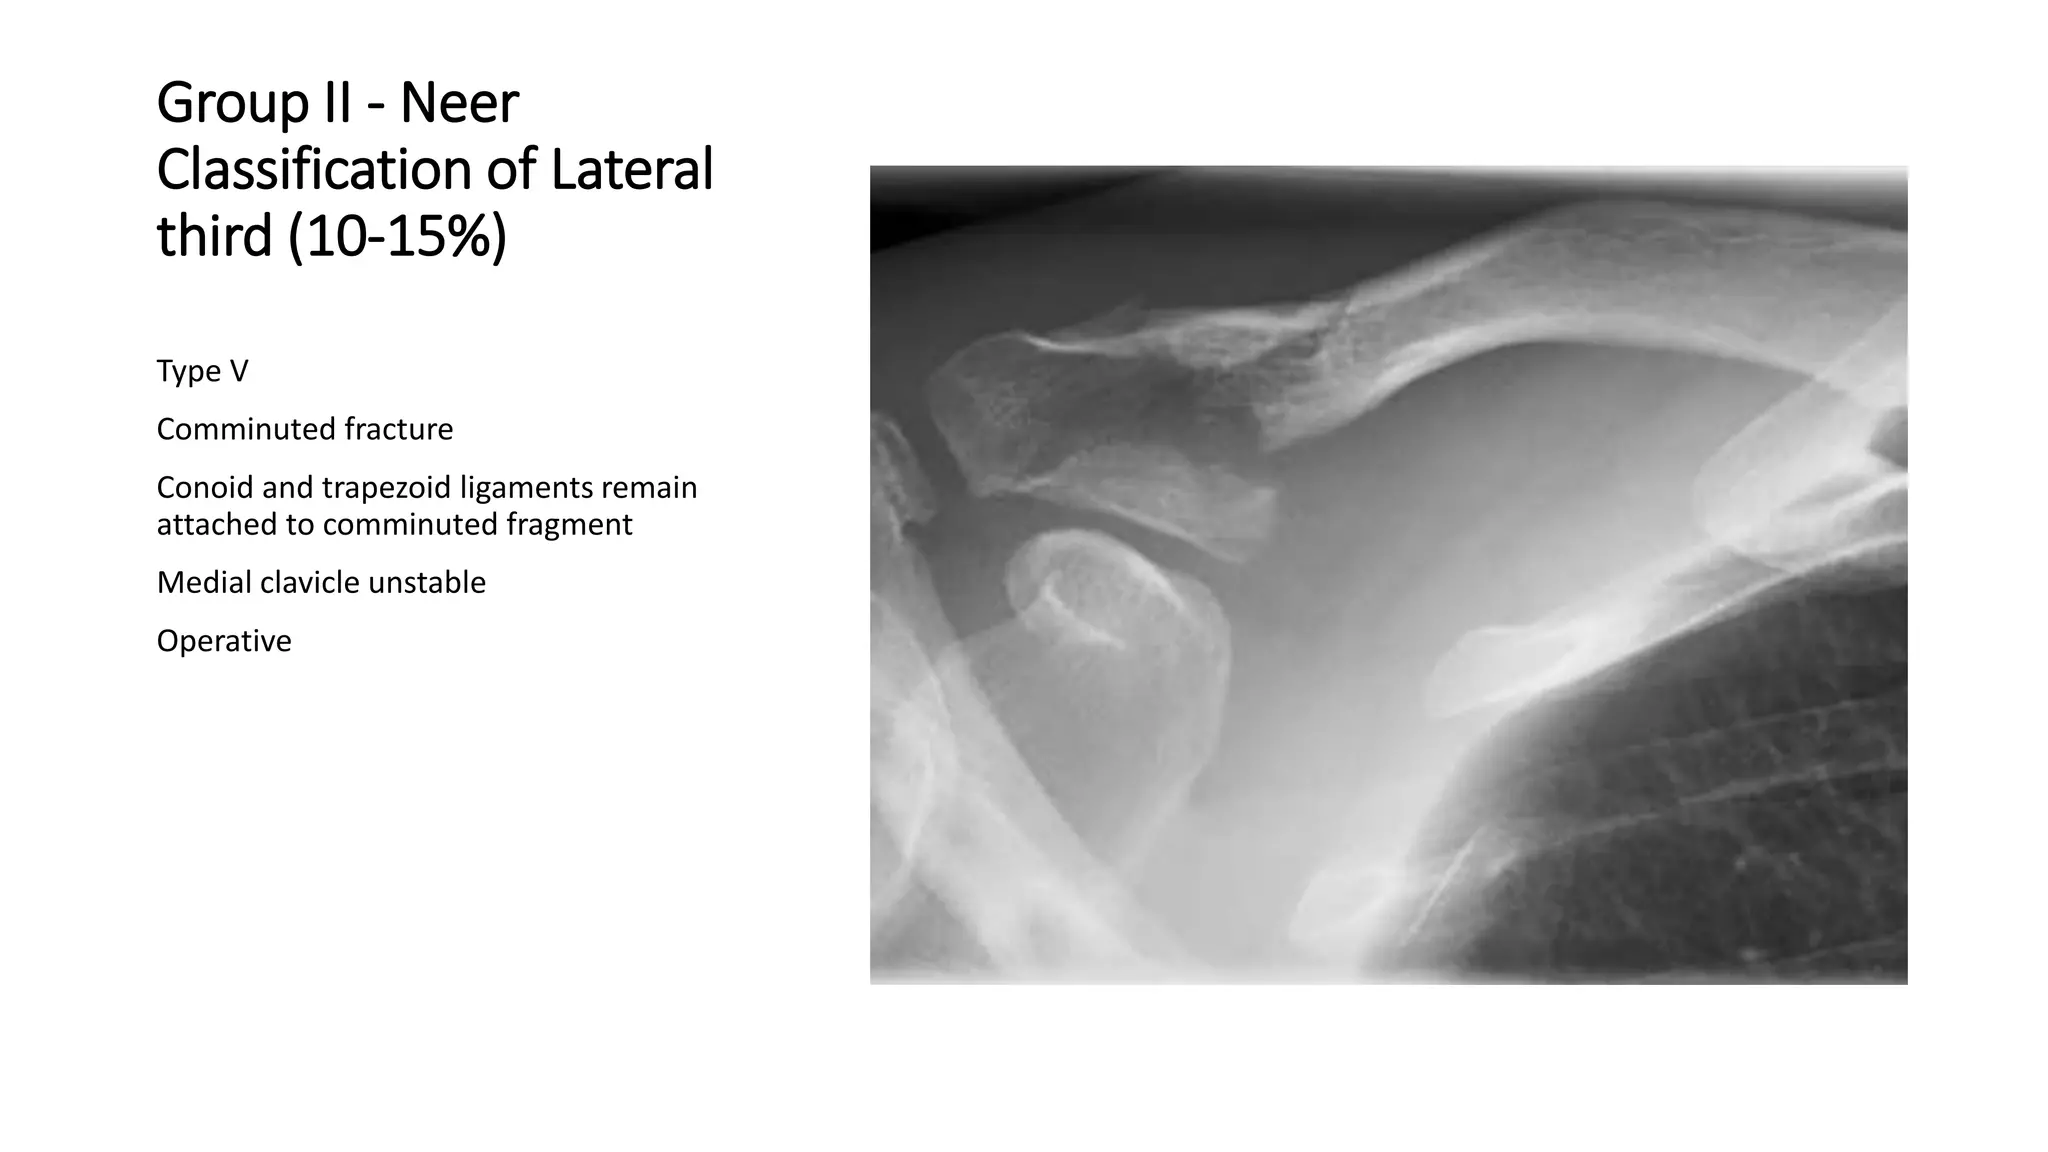

Type V

Comminuted fracture

Conoid and trapezoid ligaments remain

attached to comminuted fragment

Medial clavicle unstable

Operative